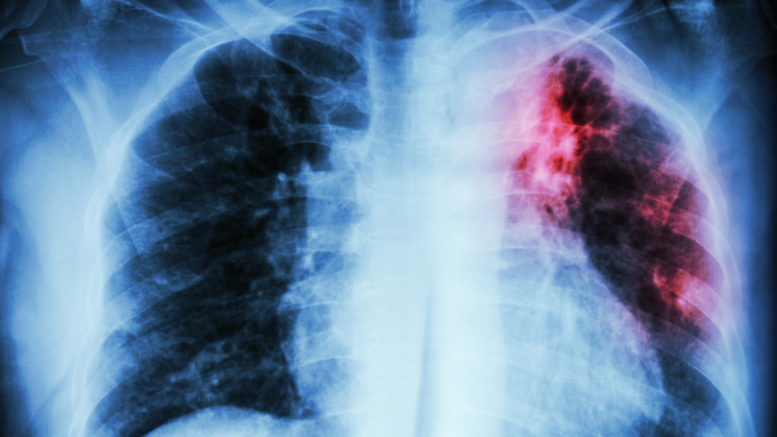

نظمت جمعية الإنقاذ من السل والأمراض التنفسية، اليوم الخميس بالدار البيضاء، لقاء تحسيسيا حول داء السل، لفائدة الأطر الطبية والساكنة بعمالة مقاطعات سيدي البرنوصي، تحت شعار “لنستثمر في الكشف عن السل من أجل الحياة”.

وهكذا، أشار المتدخلون إلى أنه رغم الجهود المبذولة والتقدم المحقق خلال السنوات الأخيرة، إلا أن وضعية هذا المرض ما زالت وبائية في المملكة، حيث أن عدد المصابين بداء السل يناهز حوالي 30 ألف حالة جديدة سنويا، أي بمعدل 82 حالة لكل 100 ألف نسمة.

وأبرزوا أن الأشخاص من 15 إلى 45 سنة، يمثلون الفئة العمرية الأكثر إصابة بهذا المرض، مع تسجيل نسبة أكبر من الذكور، الذين يمثلون حوالي 52 في المائة من المصابين بمرض السل في المغرب.

وبالنسبة لجهة الدار البيضاء- سطات، أشار المتدخلون إلى أن هذه الجهة، التي “تعتبر بيئة مواتية لبروز وانتشار هذا المرض” (كثافة سكانية، تلوث… إلخ)، تمثل 27 في المائة من مجموع مرضى السل بالمغرب، حيث تم تسجيل 7430 حالة جديدة خلال سنة 2021، أي بمعدل 99 حالة لكل 100 ألف نسمة.

وتم في إطار هذا اليوم التحسيسي، تنظيم وحدة متنقلة للفحص بالأشعة، بالمركز الطبي للقرب مؤسسة محمد الخامس للتضامن بسيدي مومن، والتي استفاد منها عشرات الأشخاص من الساكنة المحلية.